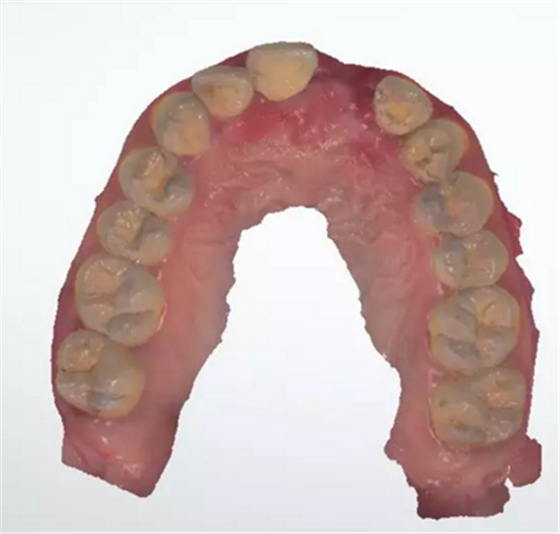

術(shù)前檢查

1.術(shù)前CT

2.術(shù)前植體設(shè)計(jì)